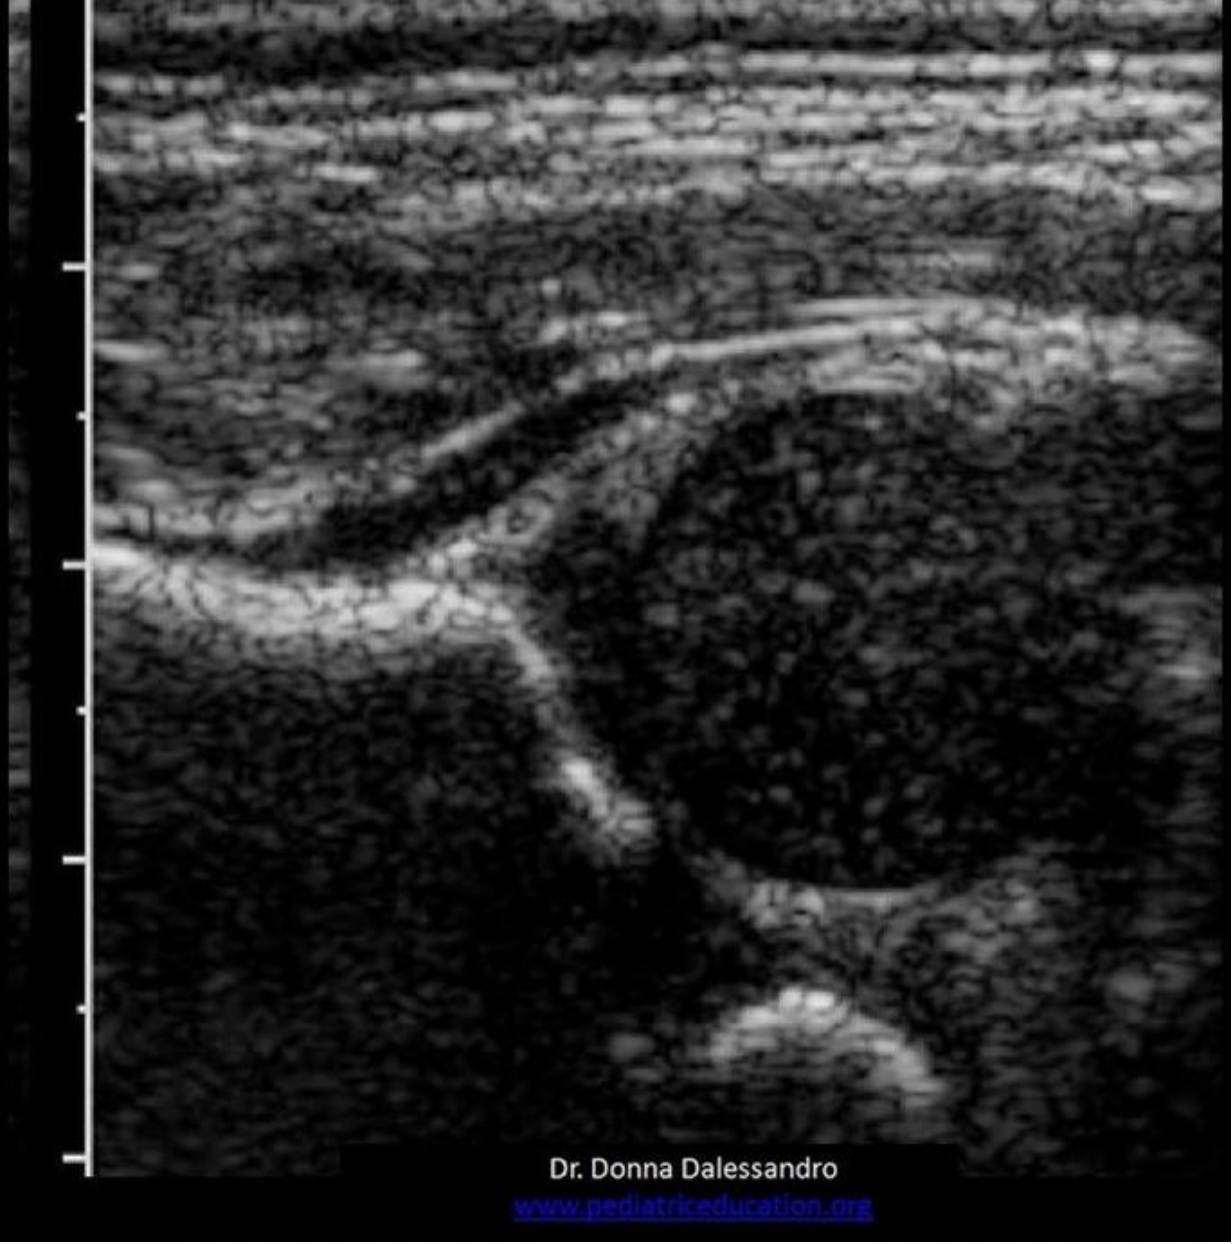

Which structure is visualized posterior and medial to the left lobe of the thyroid gland?

C. Esophagus

The strap muscles and the omohyoid muscle, one of the strap muscles, are anterior to the gland. The sternocleidomastoid muscles are anterior and lateral.

The longus colli muscles are on either side of the spine, posterior to the thyroid lobes. The esophagus is posterior and medial to the left thyroid lobe.